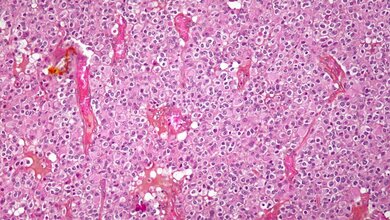

Schnelles Wachstum, starke Infiltration des umliegenden Gewebes und häufige Rückkehr auch nach erfolgreicher Therapie innerhalb weniger Monate: Das sind die Kennzeichen des sogenannten Glioblastoms. Der Tumor entwickelt sich aus dem Stützgewebe des Gehirns, den Gliazellen; er zählt zu den häufigsten Hirntumoren bei Erwachsenen. Das Glioblastoma multiforme ist die aggressivste Variante dieser Krebsart.

Mit einem neuen Ansatz will das Würzburger Team die Ausbreitung der Tumorzellen stoppen. Ein potenzieller Angriffspunkt ist bereits identifiziert: „In zurückliegenden Forschungsprojekten konnten drei Proteine als Schlüsselregulatoren für die Migration und Invasion der Tumorzellen identifiziert werden“, erklärt Tcholpon Djuzenova. Die wissenschaftlichen Namen dieser Proteine lauten Hsp90, PI3K und mTOR. Glioblastomzellen produzieren diese Eiweiße im Übermaß.